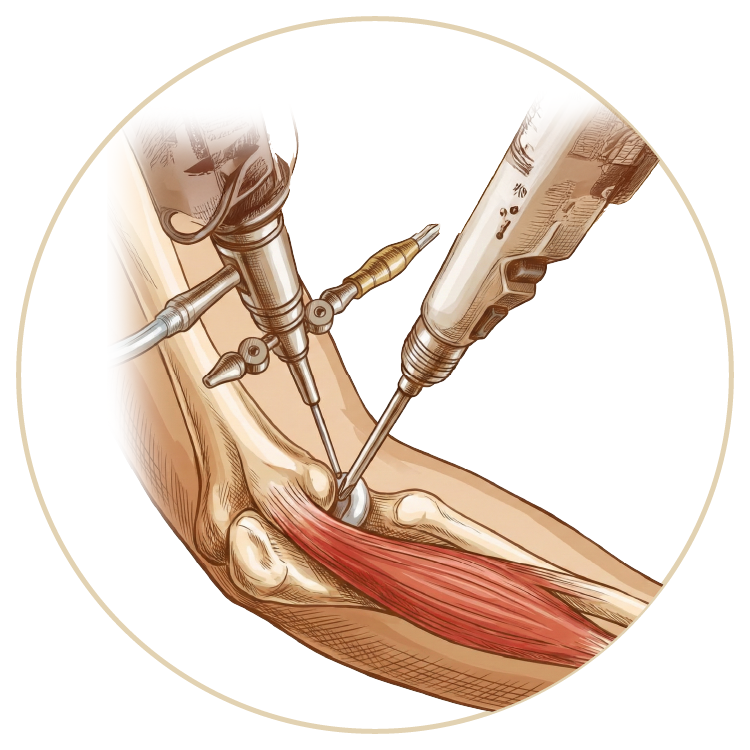

El, Bilek, Dirsek Hastalıkları ve Tedavileri

El, Bilek ve Dirsek Hastalıkları

Dirsek Yaralanmaları

Karpal Tünel Senromu

Dirsek Artroskopisi

Dirsek Protezi